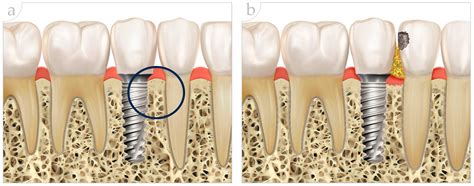

Implant Supported Prosthesis and Bone Grafting

In some cases, patients may not have enough bone density to support dental implants. This can be due to bone loss from tooth extraction, periodontal disease, or other factors. In such situations, bone grafting may be necessary to build up the jawbone and provide a stable foundation for the implants.

Bone grafting involves taking bone from another part of the body or using synthetic bone material to augment the jawbone. The grafted bone is allowed to heal and integrate with the existing bone over several months before the implants are placed.

While bone grafting adds an additional step to the implant-supported prosthesis procedure, it can significantly improve the success rate and longevity of the implants.